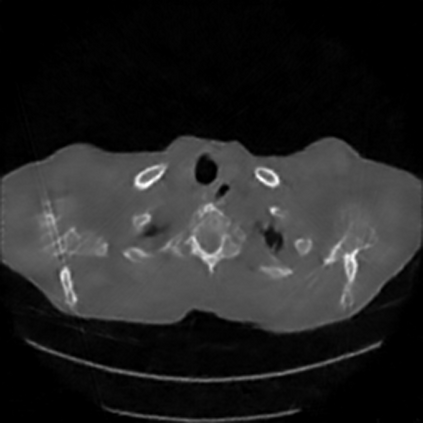

Sparse-view computed tomography (CT) -- using a small number of projections for tomographic reconstruction -- enables much lower radiation dose to patients and accelerated data acquisition. The reconstructed images, however, suffer from strong artifacts, greatly limiting their diagnostic value. Current trends for sparse-view CT turn to the raw data for better information recovery. The resultant dual-domain methods, nonetheless, suffer from secondary artifacts, especially in ultra-sparse view scenarios, and their generalization to other scanners/protocols is greatly limited. A crucial question arises: have the image post-processing methods reached the limit? Our answer is not yet. In this paper, we stick to image post-processing methods due to great flexibility and propose global representation (GloRe) distillation framework for sparse-view CT, termed GloReDi. First, we propose to learn GloRe with Fourier convolution, so each element in GloRe has an image-wide receptive field. Second, unlike methods that only use the full-view images for supervision, we propose to distill GloRe from intermediate-view reconstructed images that are readily available but not explored in previous literature. The success of GloRe distillation is attributed to two key components: representation directional distillation to align the GloRe directions, and band-pass-specific contrastive distillation to gain clinically important details. Extensive experiments demonstrate the superiority of the proposed GloReDi over the state-of-the-art methods, including dual-domain ones. The source code is available at https://github.com/longzilicart/GloReDi.